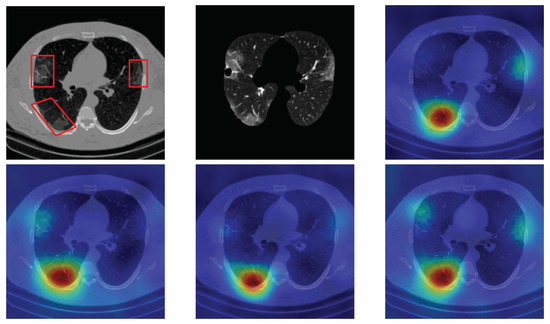

4.5. Heat Map

To have more intuition about the most important lung regions that the CNN architectures consider to classify the slice images, we used the randomized input sampling for explanations (RISE) approach [37]. Figure 13, Figure 14 and Figure 15 consist of two heat map examples of COVID-19, Cap, and normal cases, respectively. In the first example from Figure 13, we notice that despite the lung segmentation being not fully correct (it misses a considerable part of the infected region), the four CNN architectures gave more importance to the infected regions and to the lung regions in general. In the second example from Figure 13, we observe that the lung lobes were precisely segmented, and the heat maps of the four CNN architectures were well defined the infected regions, especially the Wide-Resnet-50 architecture. From both Cap examples in Figure 14, we notice that despite the lung segmentation missing considerable infected parts as well as the lung lobe regions, the heat maps of all CNN architectures give more importance to the infected region and to the lung lobes in general. This proves that the trained CNN architecture is able to define the regions of interest even when the lung lobes segmentation is not good. For the normal slice examples in Figure 15, the trained CNN architectures gave more importance to the lung lobes, especially the lower region, since the infection usually occurs there. The heat maps of COVID-19, Cap, and normal cases prove that the CNN architectures learned precisely where to look to identify the infection from the slice images.

Figure 14.

RISE heat map examples of Cap slice image using the trained multi-tasks CNN architectures (ResneXt-50, Densenet-161, Inception-v3, and Wide-Resnet-50). The first example is shown in the first two rows, where the images represent the input slice image and segmented lung lobes results, followed by the heat maps of ResneXt-50, Densenet-161, Inception-v3, and Wide-Resnet-50, respectively. The second example is in rows 3 and 4.